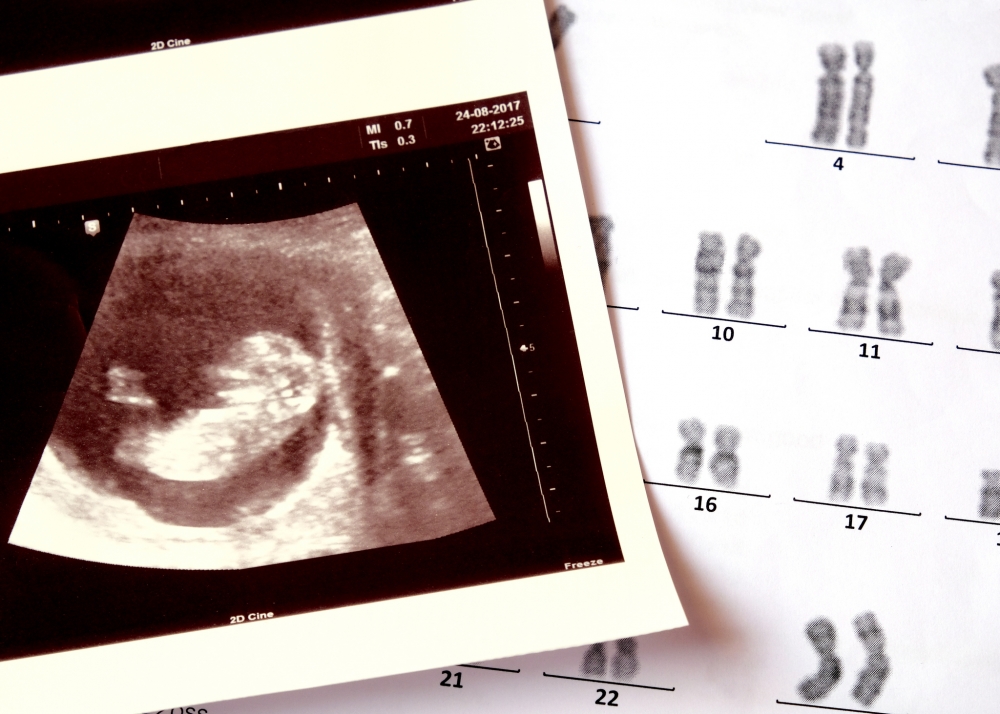

綜合外媒報道,這名身分被保護的女嬰於10月10日誕生在印度賈坎德邦。女嬰出生後,父母就發現其腹部異常腫脹,當時醫院經過電腦斷層掃描後判定女嬰腹部有腫瘤,因此將她轉介到首府的兒童醫院進行治療,並由資深的醫療團隊接手。

豈料,當主治醫生進一步為女嬰檢查後,卻發現女嬰體內藏著的根本不是腫瘤,而是更為特殊的情況——「寄生胎(Foetus in foetu,簡稱FIF)」!「寄生胎」又名「胎中胎」,常見情況有寄生雙胞胎,當其中一個孿生胚胎無法正常發育,就會被另一個胚胎吸收。更加讓醫療團隊震驚的是,女嬰體內總共發現了多達8個寄生胎,根據文獻記載,此案例在全球僅200例的同病例中,創下「最多未發育胚胎」的紀錄。

由於女嬰情況無法進行緊急手術,院方只好讓其留醫觀察。21天後,女嬰順利進入手術室,醫療團隊最終費時1個半小時的時間成功取出所有寄生胎,女嬰則恢復情況良好。主治醫生Imran博士透露,由於現在超聲波技術進步,因此「寄生胎」的情況一般在母體內就能被發現,此外,印度此前只有十例「寄生胎」案例,從新生兒身上切除的寄生胎數量最多只有2至3個,從未出現8個寄生胎的紀錄,今次情況實屬罕見。